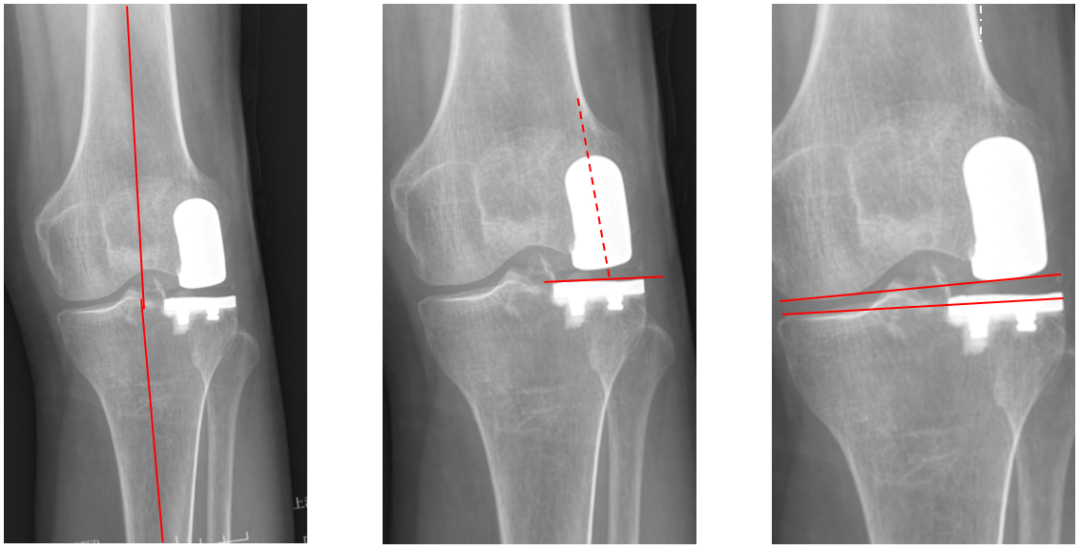

AP位胫骨与股骨假体位置:水平截骨与胫骨轴线垂直,无明显内外翻,内侧缘与胫骨平台内侧缘齐平; 股骨假体中线与胫骨假体中线一致。

标准胫骨假体位置(KA)

AP位胫骨与股骨假体位置:水平截骨与胫骨轴线 3°内翻截骨,内侧缘与胫骨平台内侧缘齐平; 股骨假体中轴线与胫骨假体垂直,股骨假体中线与胫骨假体中线一致。

胫骨假体内翻

AP位胫骨与股骨假体位置:胫骨假体内翻10°,股骨假体中轴线与胫骨假体垂直。